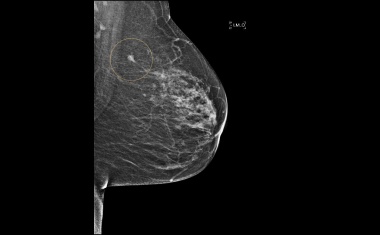

Dexamethason könnte Brustkrebs-Metastasen reduzieren

Das Medikament Dexamethason ergänzt Krebsbehandlungen, um Nebenwirkungen der Chemotherapie wie etwa Übelkeit und Entzündungen zu mildern. Forschende der Universität Basel haben nun entdeckt, dass es darüber hinaus auch Metastasen bei bestimmten Typen von Brustkrebs bekämpft.